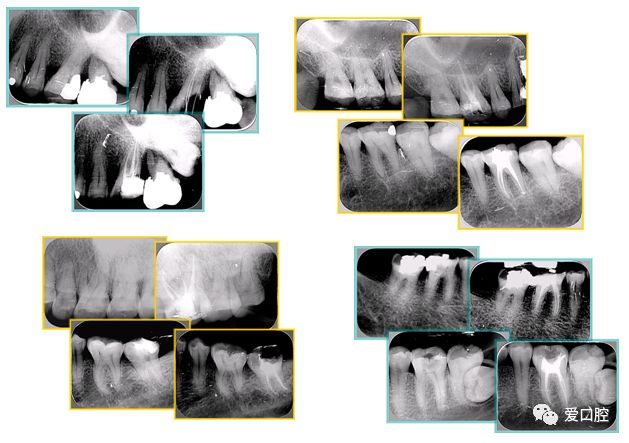

6. 术后 X 线片

术后 X 线片用来评定根管充填 长度、致密度(管壁清晰、侧枝)等指标。

左图为根管充填术后 X 线片。图中可见,根管充填较好。右下图有白色小点,为侧方加压导致糊剂挤出所致,表明根管充填比较致密。

致密、恰到好处的充填可去除干净根管里感染灶,机体逐渐恢复。

牙胶尖什么颜色根管治疗的标准步骤以及治疗细节的把握_https://www.jmylbn.com_新闻资讯_第20张

多根牙时候需进行偏移投照,正位投照无法说明具体哪根牙根管充填效果。